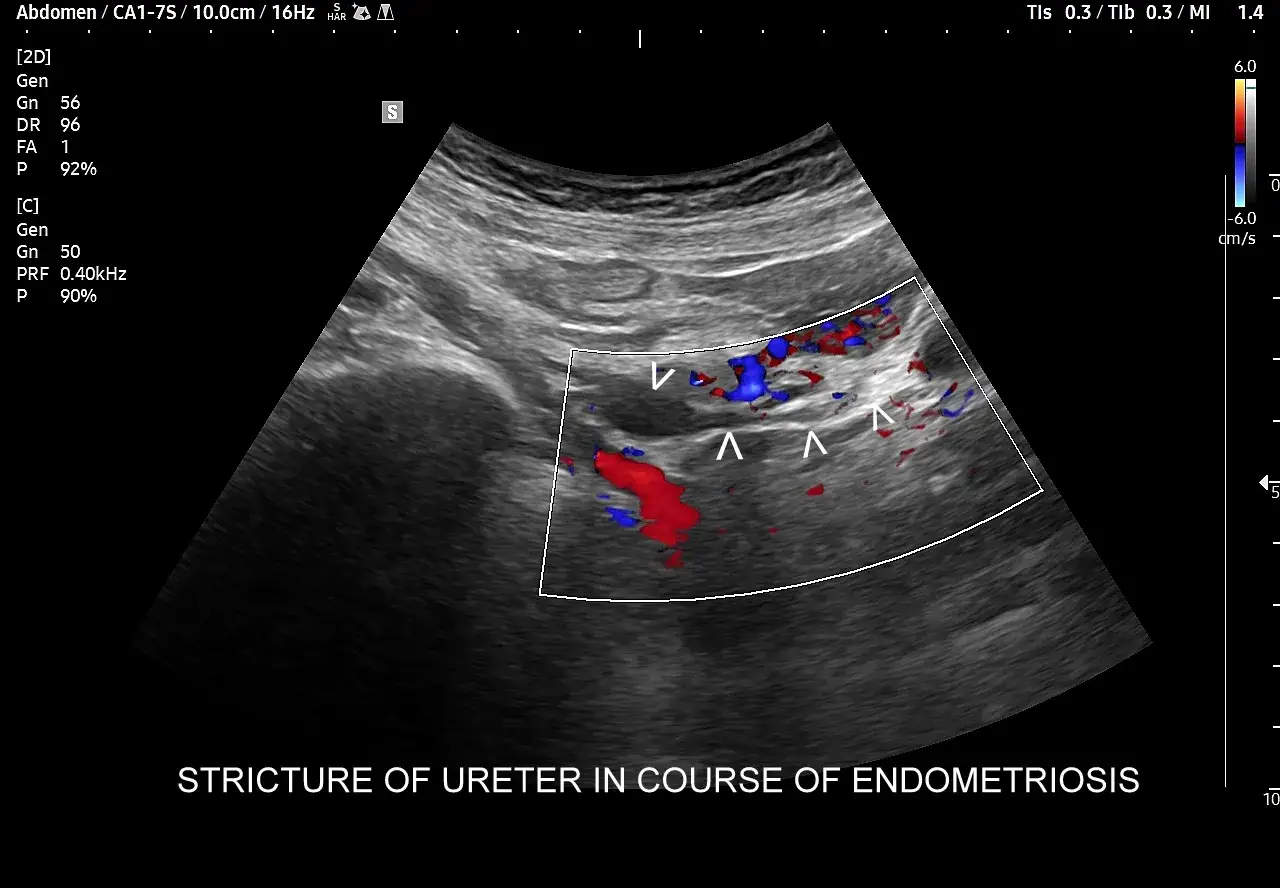

Po wstępnym wywiadzie i badaniu fizykalnym, lekarz często zleca badania obrazowe. Kluczowe w diagnostyce endometriozy jest specjalistyczne badanie ultrasonograficzne (USG), często wykonywane przez doświadczonego specjalistę, który potrafi ocenić narządy miednicy mniejszej z dużą dokładnością. Szczególnie cenne jest USG przezpochwowe z użyciem sondy o wysokiej częstotliwości, które pozwala na uwidocznienie ognisk endometriozy, torbieli endometrialnych (tzw. "torbieli czekoladowych") czy zrostów. W bardziej skomplikowanych przypadkach, gdy istnieje podejrzenie głębokiej endometriozy naciekającej na narządy jamy brzusznej, lekarz może zlecić rezonans magnetyczny (MRI), który daje jeszcze bardziej szczegółowy obraz tkanek.

- Stopień IV (ciężki): Choroba jest zaawansowana, z licznymi, głębokimi ogniskami, dużymi torbielami endometrialnymi na obu jajnikach, rozległymi zrostami, a czasem z naciekaniem innych narządów, np. jelit czy pęcherza moczowego.